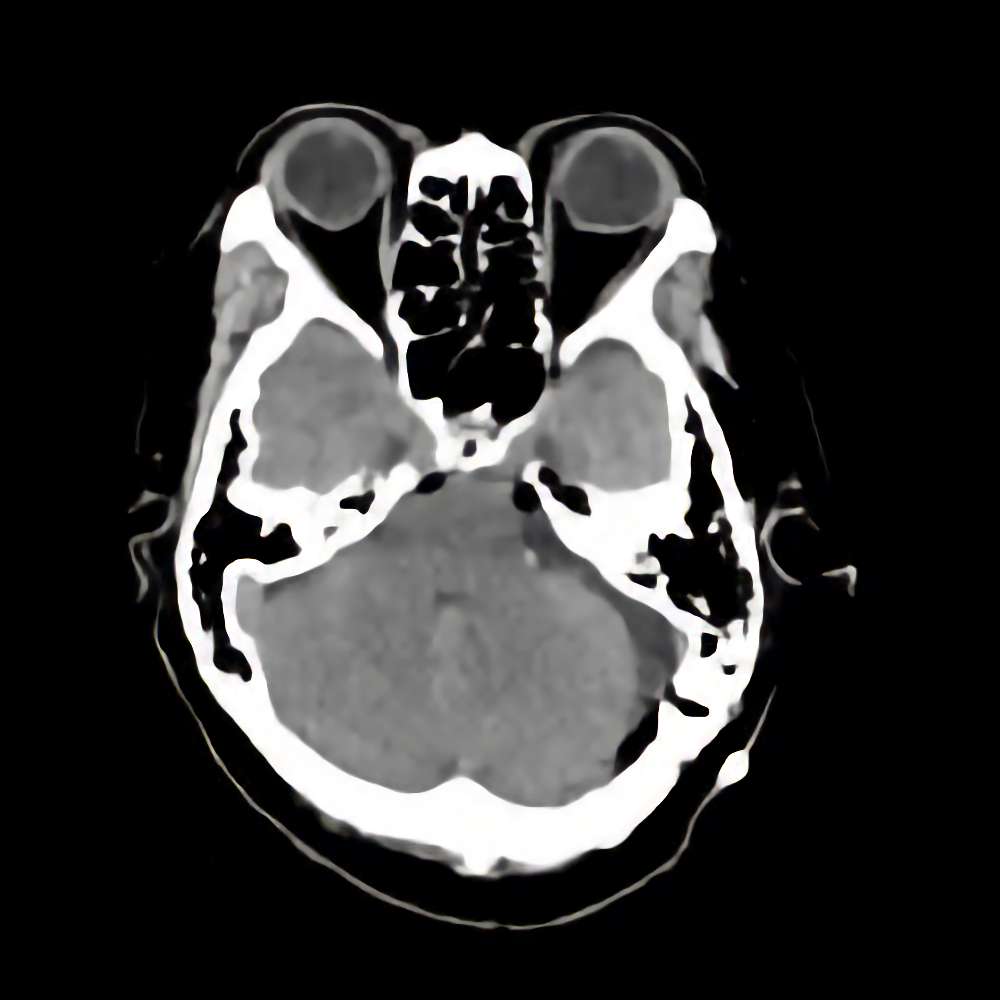

症例 '16年5月

No.

年_番号

手術年月

患者年齢

’16_69

'16年5月

70代

病名

術式

備考

左聴神経腫瘍

断層撮影

手術前

1

手術前2

手術後